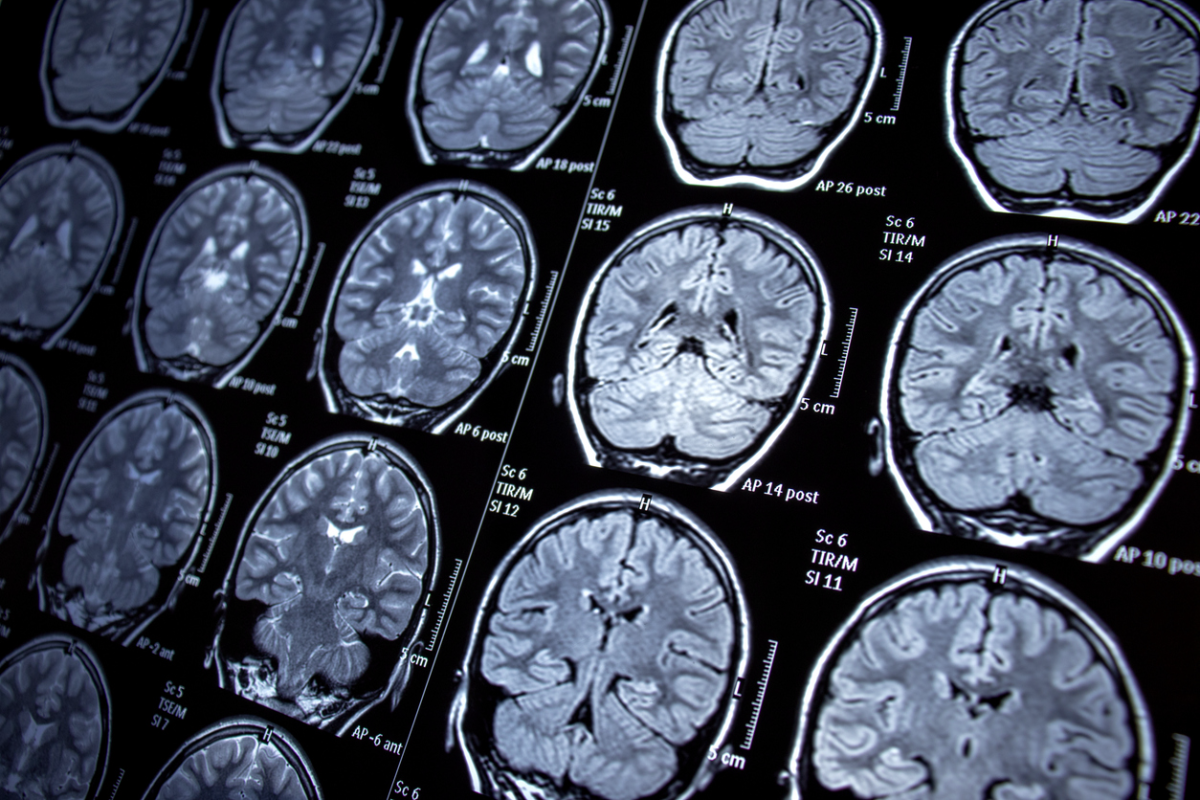

Understanding the Psychological Effects of Brain Tumors

A brain tumor diagnosis is a life-changing event that affects both physical and mental well-being. The impact extends far beyond the tumor itself, influencing emotions, thought processes, and behaviors.

The Impact of Brain Tumors on Mental Health

A brain tumor diagnosis affects more than just physical health—it can deeply impact mental well-being. The emotional and cognitive toll of both benign and malignant brain tumors is significant, and understanding these effects can help patients and caregivers navigate the journey with greater clarity.